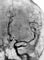

При подозрении на подоболочечное кровоизлияние , обусловленное аневризмой сосудов головного мозга, проводят церебральную ангиографию, которая позволяет выявить церебральный ангиоспазм (рис. 3) Крупные аневризмы могут быть выявлены также с помощью компьютерной томографии. Ангиография, проведенная после субарахноидального кровоизлияния, не выявляет его причины у 10—30% больных, что может объясняться наличием ангиоспазма, а также частичного или полного тромбирования шейки аневризмы. Полому при повторно произведенной ангиографии количество больных с первоначально не выявленной аневризмой уменьшается. Методом диагностики и контроля ангиоспазма является транскраниальная допплерография, позволяющая оценивать линейную скорость кровотока во всех магистральных сосудах головного мозга, все этапы нарастания ангиоспазма и его обратного развития.